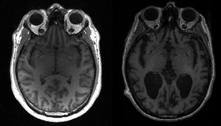

Cientistas descobrem os motivos do avanço do Alzheimer no cérebro